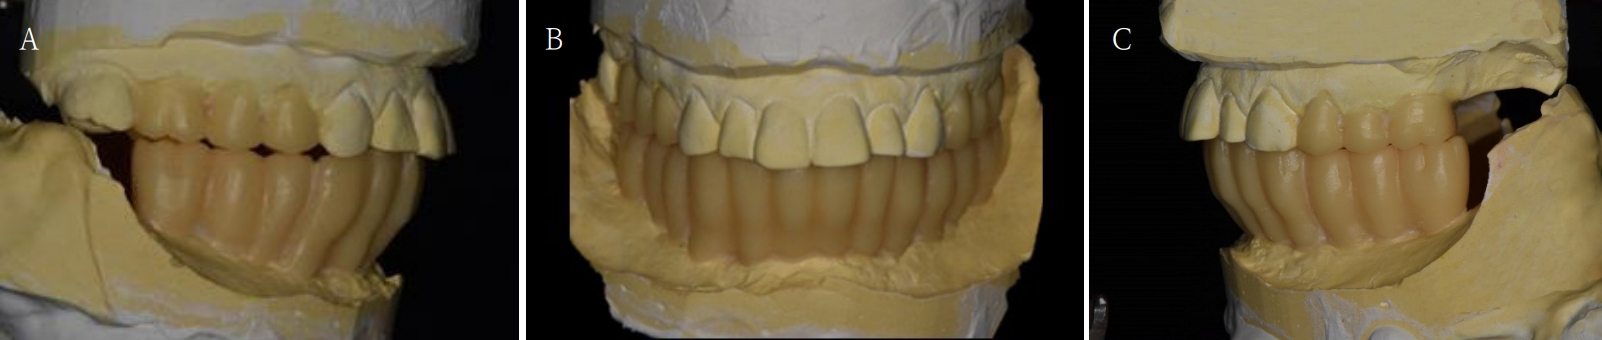

Fig. 4.

Ideal occlusal plane is developed with diagnostic wax up model. A. Right side view. B. Frontal view. C. Left side view.

jkda-2025-63-7-001f4.jpg